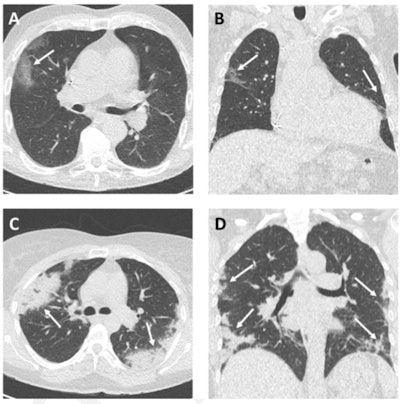

To find out, Dangis's team conducted a study of 192 emergency room patients with COVID-19 symptoms who underwent low-dose submillisievert chest CT as well as RT-PCR testing between March 14 and 24. The CT protocol consisted of the following: 100 kVp, 20 mAs, a pitch of 1.2, and gantry rotation time of 0.5 seconds.

The group found that low-dose submillisievert chest CT performed well across a variety of measures, especially in patients with symptoms for more than 48 hours:

Dangis and colleagues also found that the mean effective radiation dose for their low-dose chest CT protocol was 0.56 mSv. Median time between the acquisition of the CT images and the patient report was 25 minutes (range: 13-49 minutes). Intra- and interreader agreement for the CT exams was 0.96 and 0.95.